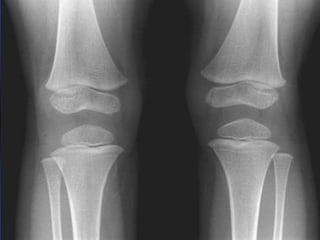

Acute Lymphoblatic Leukemia

Bone cyst

Lucent metaphyseal bands (arrows), a finding

present in 90% of patients with leukemia.